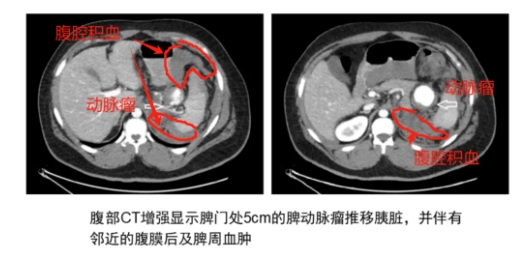

(2)脾动脉瘤破裂时影像学表现

脾动脉瘤的确诊首选CTA。

血管造影是金标准,可以明确动脉瘤的确切位置、大小、毗邻关系,还可以同时行介入治疗。